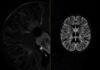

- Точная диагностика: обязательно пройти все необходимые обследования, в том числе ЭЭГ и МРТ.